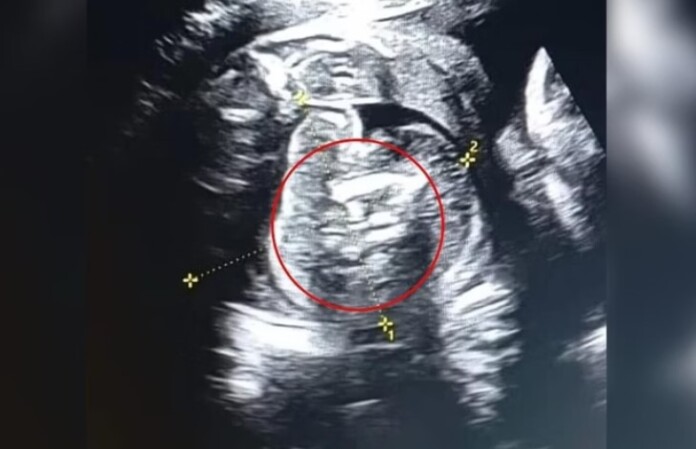

Uma mulher indiana de 32 anos foi surpreendida na 35ª semana de gestação ao descobrir que seu bebê carregava dois fetos dentro do abdômen. O caso raríssimo, conhecido como “feto dentro de feto”, foi relatado por médicos do Buldhana Women’s Hospital.

Esse fenômeno ocorre quando um embrião é absorvido pelo irmão gêmeo durante a gestação. Casos envolvendo múltiplos fetos são ainda mais incomuns, com apenas cerca de 200 registros na literatura médica.

O parto aconteceu em 1º de fevereiro. Após o nascimento, os médicos removeram os dois fetos do abdômen do bebê. Eles haviam parado de crescer durante a gestação e não possuíam órgãos vitais completamente formados. Tanto a mãe quanto a criança passam bem.